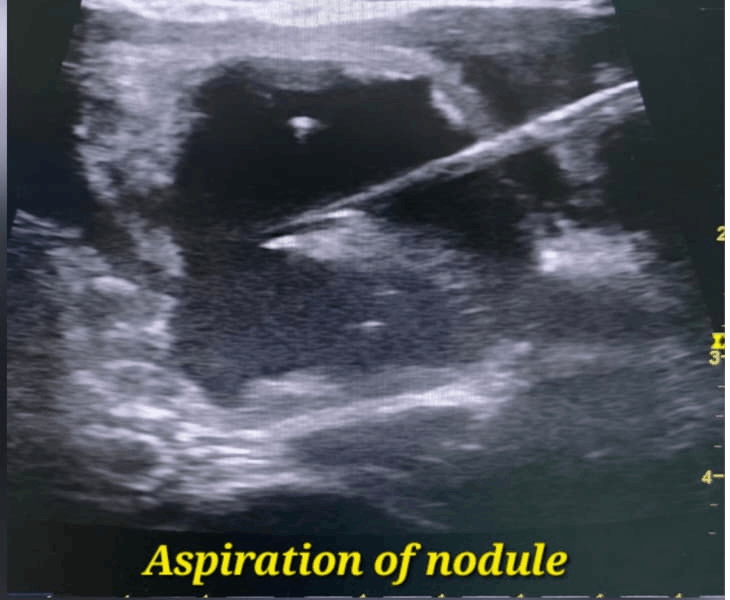

- Aspiration of nodule: fluid is removed from cystic nodules to reduce size and relieve pressure.

Depending on the nodule type, treatment may be done in stages under ultrasound guidance: